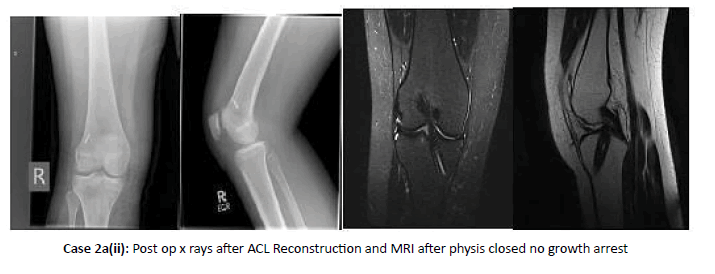

Case 2: ACL injury with open physis

ACL injury with open physis is shown in Case 2a, 2b, 2c and 2d

Note: The treatment of ACL tears in the paediatric population is challenging and controversial. Younger age Patients group (5-12) with open physis were offered the option of activity modification, functional bracing, rehabilitation, and careful follow-up. Surgery was indicated in skeletally immature patients with a torn ACL and an additional repairable meniscal injury and in patients who failed conservative care. Another option for the completely immature paediatric athlete was a more technically demanding all-epiphyseal procedure using hamstring tendon grafts.

In the mid-age child (skeletal age 12 to 14 in girls and 13 to 16 in boys), physeal-sparing methods may be selected; however, many of these intermediate-maturity patients were safely and more appropriately treated with transphyseal reconstruction using small 7 mm-8 mm centrally placed drill holes and a soft tissue graft, such as the hamstring tendons. Patients and parents were counselled that there remains a small risk of physeal injury and a possibility of additional surgery for angular or growth disturbance. Last, adolescents who are approaching skeletal maturity (skeletal age older than 14 in girls and older than 16 in boys,) were undergone anatomic ACL surgery with tibial and femoral drill holes and hamstring graft with minimal risk of physeal injury.